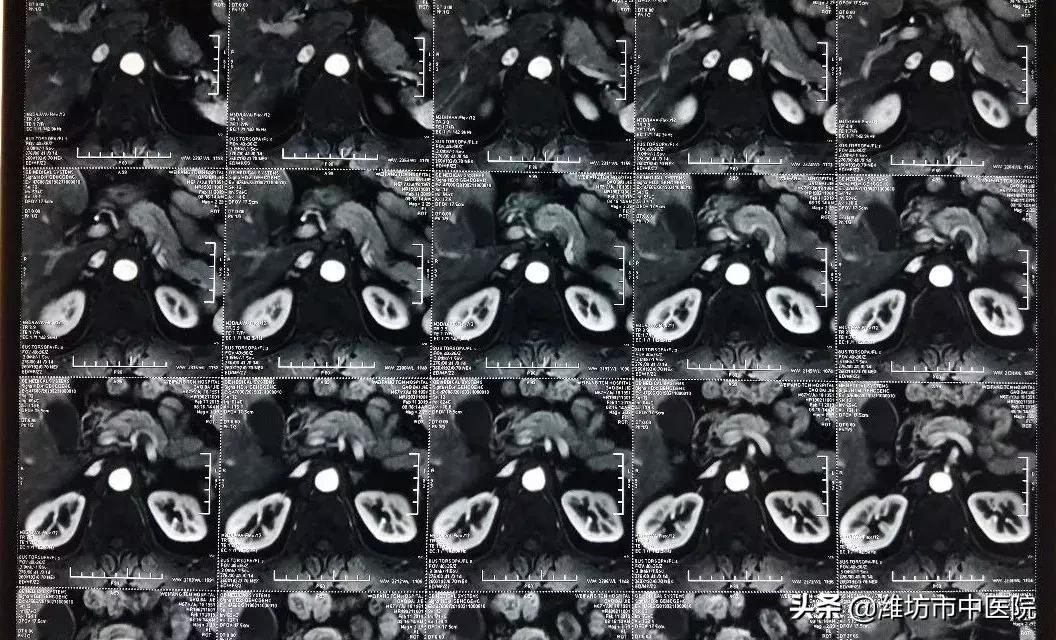

患者高先生来我院胸外科进行手术治疗,然而术前检查发现左侧肾上腺肿物,转移瘤不除外。

肾上腺MRI检查显示左肾上腺结节